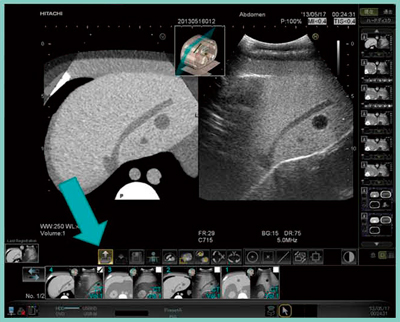

新しくRVSに搭載されたレジストレーション機能では,同一検査内で登録した位置情報を容易に呼び出すことが可能となった。液晶パネルのレジストレーション機能ボタンを選択すると,登録した過去画像のサムネイルが表示される。その中から,見たい部位の画像を選択するだけで,その部位での位置合わせが行われる(図2)。さらに,この機能はプローブを変更しても使用可能で,コンベックスプローブで位置合わせ後に,穿刺用マイクロコンベックスプローブに換えても,レジストレーション機能で同じ位置情報を呼び出して,簡単に位置合わせを行うことができる。

このようにレジストレーション機能は,複数病変の観察や肋間を変えて穿刺治療を行う場合,また,観察時と穿刺時でプローブの角度・種類を変える場合などに,非常に高い有用性を発揮する。

図2 RVSの“レジストレーション機能”